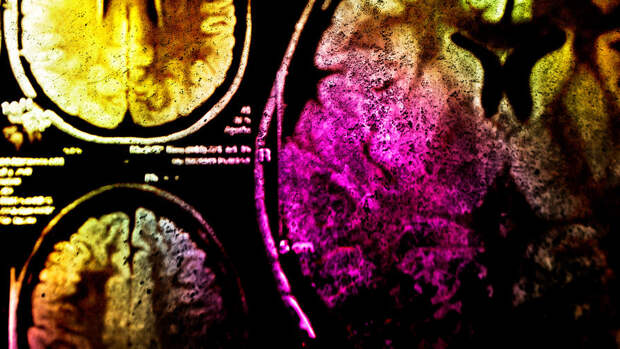

Исследователи из Гарвардской школы инженерии и прикладных наук имени Джона А. Полсона (SEAS) и Массачусетского технологического института разработали новый метод воздействия на клетки головного мозга, который позволит лечить эпилепсию и аутизм. Исследование опубликовано в журнале Science Advances.